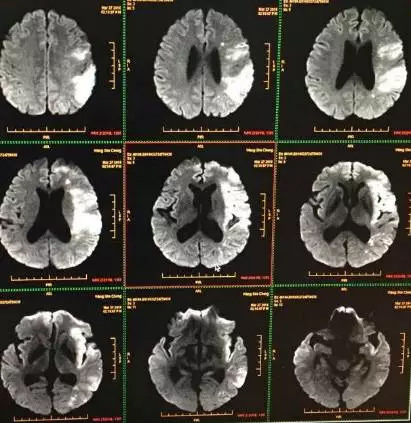

男性患者,51岁,以“言语不能、右侧肢体偏瘫3.5小时”入院,神经系统查体:神志清楚,完全性失语,查体不能合作,右侧上下肢体肌力2-3级。NIHHS评分=12分。

急诊颅脑CT排除出血,患者已超出静脉溶栓时间窗,予性颅脑MRI+MRA示“左侧大脑中动脉供血区大面积脑梗死,左侧大脑中动脉闭塞”。